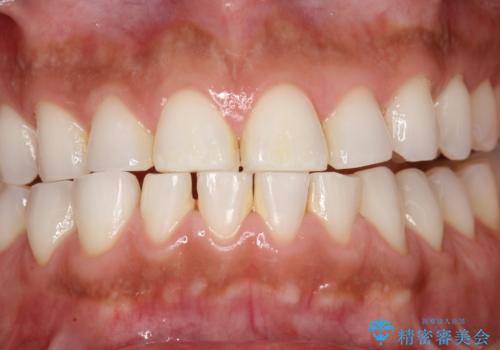

ホワイトニング 1日で真っ白な歯に

- ホワイトニングで歯を白くしたいとのことでした。

処置前クリーニング¥3300・オフィスホワイトニングのエクセレントコース¥29700を行いました。

- ¥33000費用は治療当時の料金となります